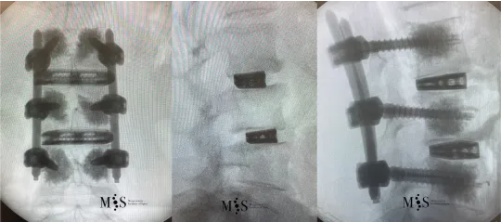

The images show post-operative correction of the lumbar spine after OLIF surgery of the previouslky mentioned case. Note how the scoliosis has been corrected in the front plane (image on the left) and the instability has been corrected on the side (image on the right) with interbody cages with a big footprint. A few hours after surgery this patient was already walking by her own (see video below) and she was discharged from the hospital in less than 24 hours.